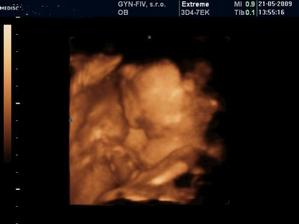

8.3. - 3D UTZ - vraj to bude dievcatkooooooo :o))

21.5. dievcatko potvrdene, tak sa tesiiiiime :o). Vsetko je ok, tak uz nakupujeme vybavicku :o)